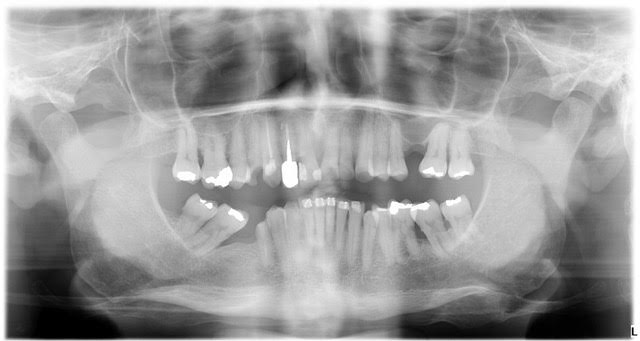

Riabilitazione implanto-protesica completa di paziente disfunzionale, con molteplici fratture ed abrasioni.